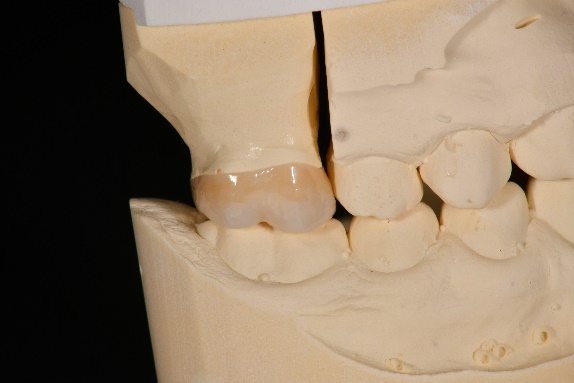

Lateral view of the finalized crown of tooth 16. Cervical part was individualized with stains.

Lateral view of the finalized crown of tooth 26. Cervical part was individualized with stains

Lateral view of tooth 16 immediately before adhesive cementation.